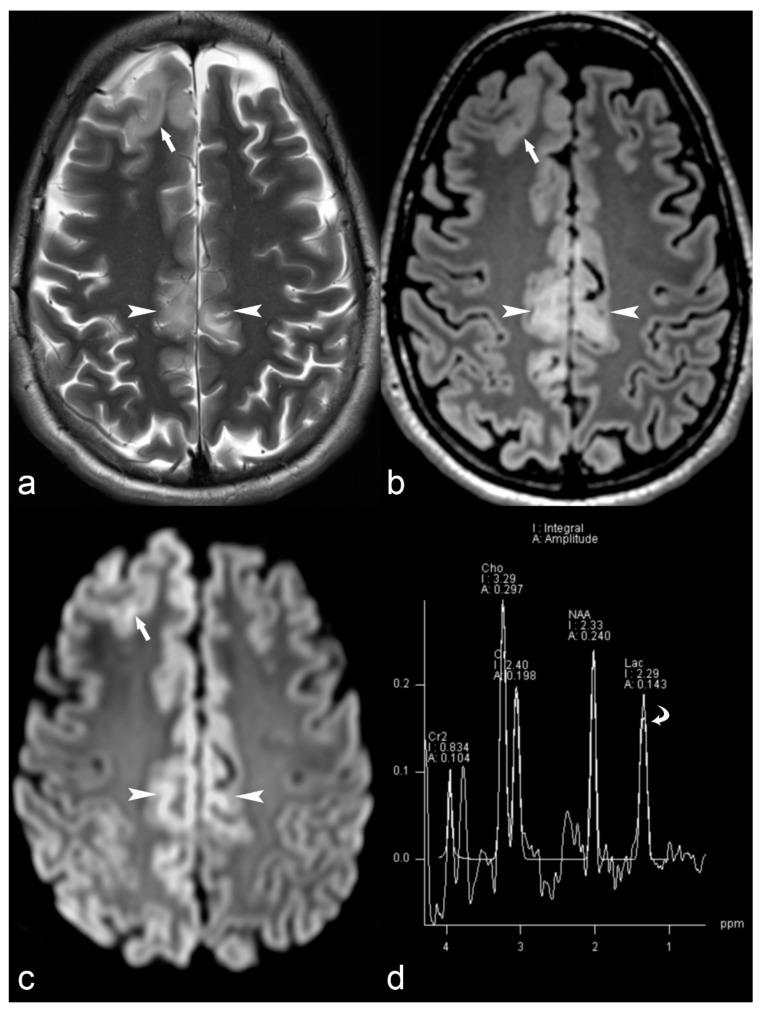

The etiology of epilepsy is variable and sometimes multifactorial. Clinical course and response to treatment largely depend on the precise etiology of the seizures. Along with the electroencephalogram (EEG), neuroimaging techniques, in particular, magnetic resonance imaging (MRI), are the most important tools for determining the possible etiology of epilepsy. Over the last few years, there have been many developments in data acquisition and analysis for both morphological and functional neuroimaging of people suffering from this condition. These innovations have increased the detection of underlying structural pathologies, which have till recently been classified as "cryptogenic" epilepsy. Cryptogenic epilepsy is often refractory to anti-epileptic drug treatment. In drug-resistant patients with structural or consistent functional lesions related to the epilepsy syndrome, surgery is the only treatment that can offer a seizure-free outcome. The pre-operative detection of the underlying structural condition increases the odds of successful surgical treatment of pharmacoresistant epilepsy. This article provides a comprehensive overview of neuroimaging techniques in epilepsy, highlighting recent advances and innovations and summarizes frequent etiologies of epilepsy in order to improve the diagnosis and management of patients suffering from seizures, especially young patients and children.